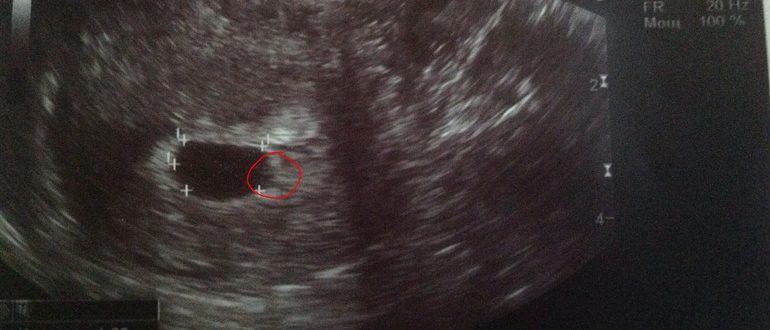

Узи не видит плод

Когда на УЗИ можно увидеть плодное яйцо в матке и почему его бывает не видно Когда на УЗИ становится видно плодное яйцо в матке, беременность считается подтвержденной. Но…